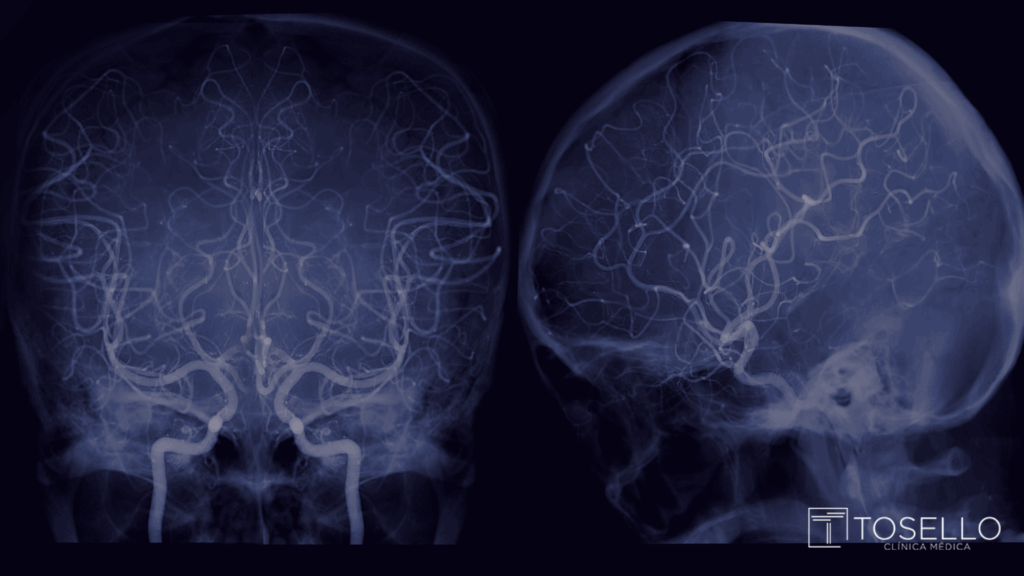

O neurorradiologista intervencionista é um médico especializado em diagnosticar e tratar doenças vasculares neurológicas através de procedimentos guiados por imagem. Isso significa que ele utiliza exames como angiografia cerebral, ressonância magnética e tomografia para realizar intervenções de forma precisa, sem grandes cortes cirúrgicos.

Entre os principais procedimentos realizados estão:

- Embolização de aneurismas cerebrais

- Tratamento de malformações arteriovenosas (MAVs)

- Trombectomia para AVC isquêmico

- Tratamentos de tumores e lesões vasculares